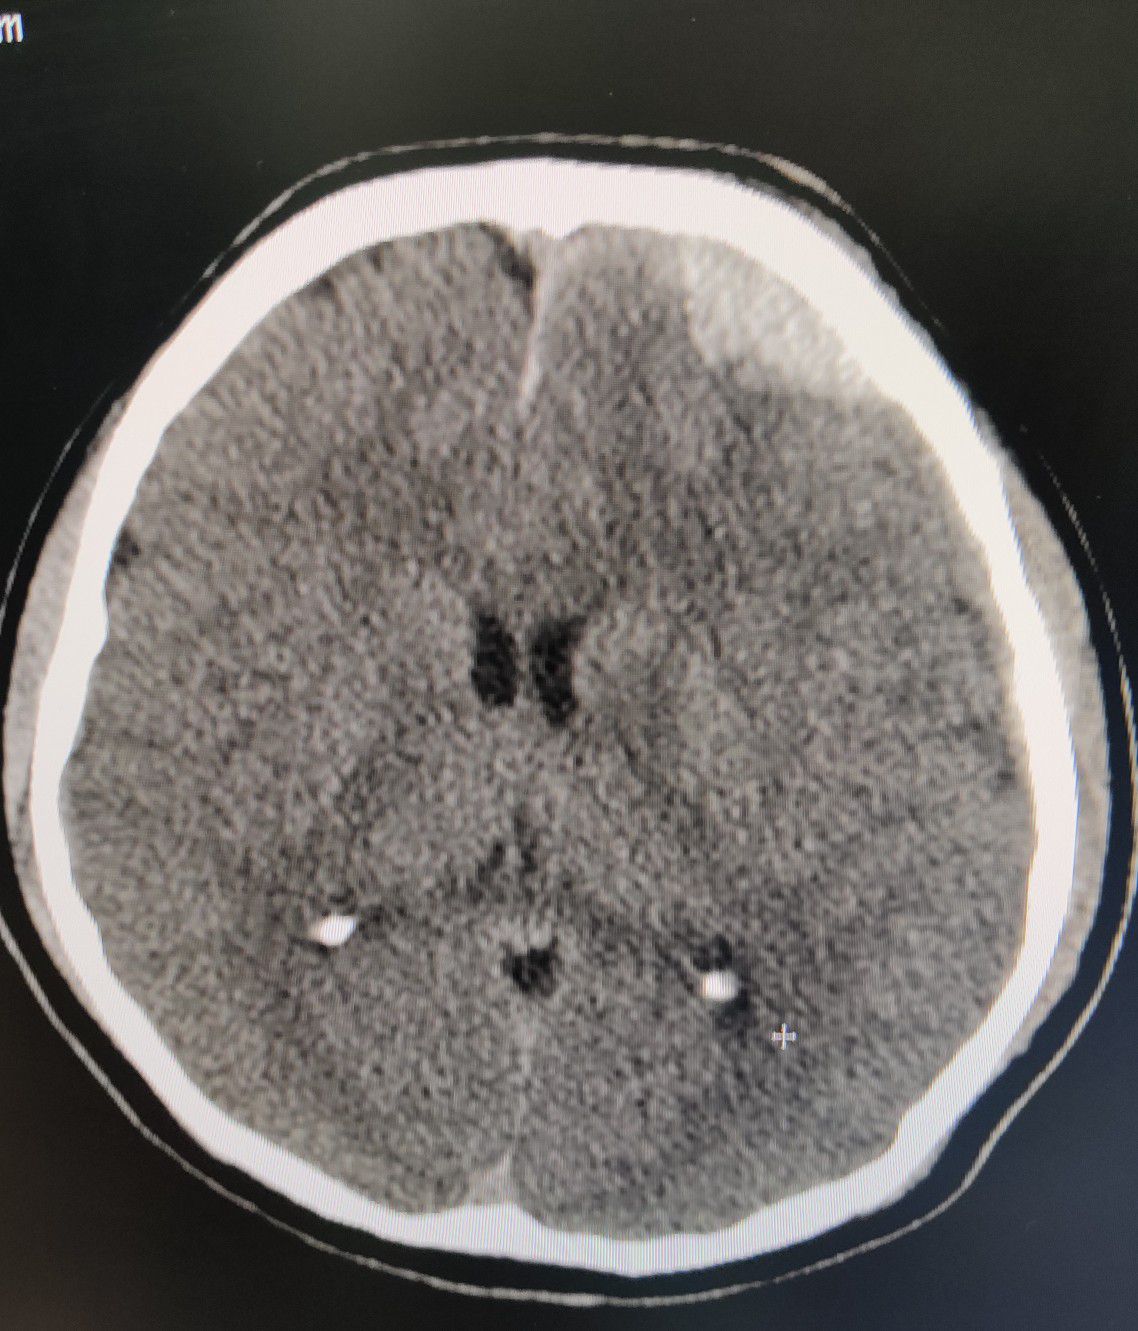

EDH CT BRAIN

Brain

Ctscan

Edh